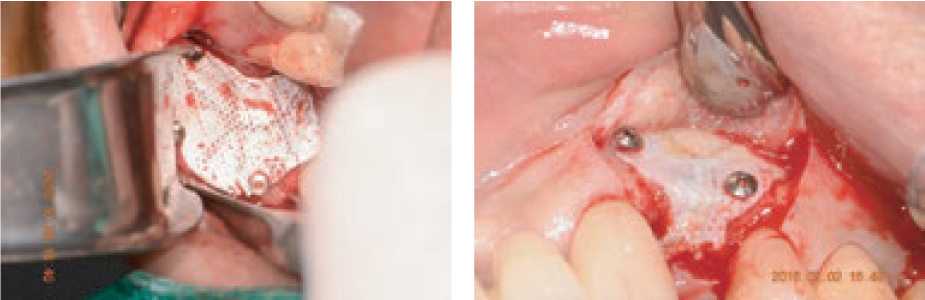

BIO-MEM

Non-Resorbable Micro Pore PTFE Membrane

This is a non-resorbable PTFE membrane made of Micro Pore PTFE

and Titanium preventing growth of bacteria

while being facilitating cellular adhesion to the surface and

plasma protein absorption upon implantation.

and Titanium preventing growth of bacteria

while being facilitating cellular adhesion to the surface and

plasma protein absorption upon implantation.

Predictable & controlled resorption

Protects the graft area from unwanted soft tissue infiltration

during the initial phase of healing.

Resorbs predictably over 3 to 4 months as new host collagen is

simultaneously regenerated.

during the initial phase of healing.

Resorbs predictably over 3 to 4 months as new host collagen is

simultaneously regenerated.

Highly purified porcine peritoneum and minimal crosslinking

The intact tissue of porcine peritoneum provides inherent strength

which is further minimally crosslinked,

leading to predictable resorption

and desirable handling characteristics.

which is further minimally crosslinked,

leading to predictable resorption

and desirable handling characteristics.